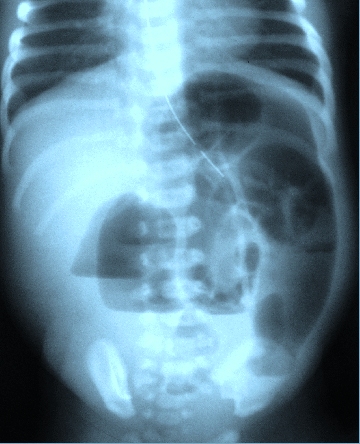

Colonic atresia and stenosis are rare causes of intestinal obstruction in the infant. Only 10 cases have been reported in Literature since 1966 and only one late-onset case has been reported in Literature until now. We describe the case of a 3 day old baby presenting with abdominal distension, failure to pass meconium and vomiting. X-ray of the abdomen showed dilated gut loops. Exploratory laparotomy was performed. At the junction of descending and sigmoid colon a stenosis was found, laparotomy also revealed a perforation of transverse colon. Transverse colostomy and a mucous fistula of sigmoid colon was performed after resecting stenosing segment and colon distal to perforation site upto stenosing site. Diagnosis was confirmed on histopathology. Colostomy was close after six weaks with uneventful recovery. Considering both the Literature and our case, congenital colonic stenosis should be considered one of the rare differential diagnoses in a neonate presenting as complete or partial intestinal obstruction.

- X-RAY ABDOMEN SHOWING MULTIPLE AIR FLUID LEVELS AND DISTENDED GUT LOOPS